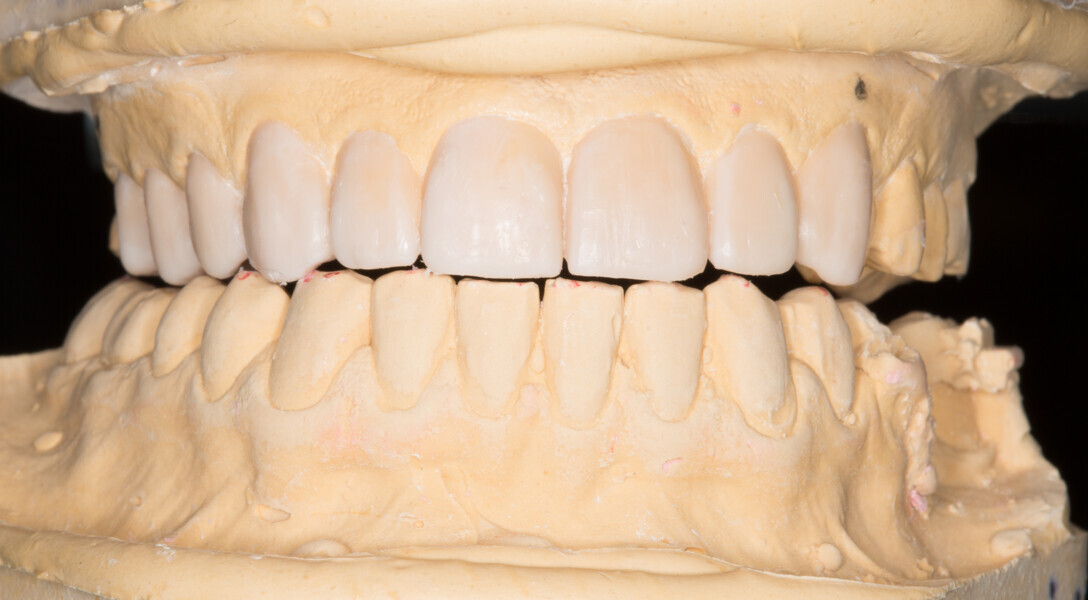

Fig. 5: Functional analysis wax-up.

Fig. 6: Functional analysis wax-up.

Fig. 7: Functional analysis wax-up.